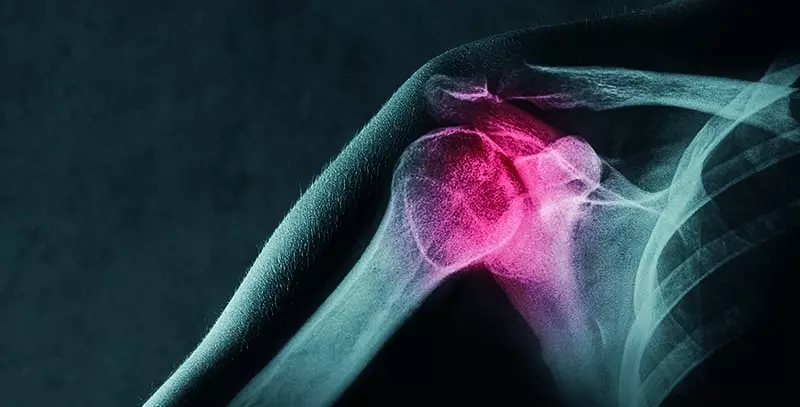

Uprawianie sportu zarówno tego zawodowego, jak i rekreacyjnego wiąże się z możliwością wystąpienia urazów aparatu ruchu. Zakres oraz rodzaj uszkodzeń jest różny, jednak właściwe postępowanie, adekwatne do zaistniałych niekorzystnych zmian, może zmniejszyć niekorzystne skutki w przypadku wszystkich rodzajów uszkodzeń.

Urazy powodujące uszkodzenia tkanek są bodźcem do zapoczątkowania procesu samoleczenia, którym paradoksalnie jest stan zapalny. Tym, co możemy zaobserwować, są: ból i związane z nim ograniczenie aktywności okolicy dotkniętej urazem, obrzęk, zaczerwienienie, ucieplenie, zasinienie i/lub krwiak. Włączenie naszych działań w fizjologiczne procesy leczenia i podporządkowanie się im wpłynie korzystnie na przyspieszenie powrotu do sprawności.